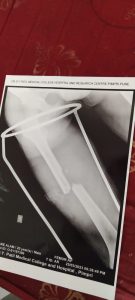

महाराष्ट्र राज्य रूग्णसेवक संघटनेच्या भोसरी विधानसभा अध्यक्ष असलेल्या पातूर तालुक्यातील सती आसोला येथील संदीप चव्हाण याचा रात्री एक वाजता मोबाईल वाजला…त्यानी तो फोन उचलला… समोरून एका व्यक्तीने त्याला सांगितले की माझ्याकडे कामगार म्हणून काम करणाऱ्या कामगाराचा अपघात होवून एका पायातील मांडीच्या हाडाचे दोन तुकडे झाले आहे खासगी रुग्णालयात उपचारासाठी डाॅक्टरांनी रूपये दोन लाख खर्च सांगितले आहे त्याची परिस्थिती जेमतेम असल्याने तो खर्च त्याला न झेपावणारा आहे तसेच तो उत्तरप्रदेश चा रहिवासी असल्याने त्याचे कुणी नातेवाईक पुण्यात नाही त्यामुळे आपल्या संघटनेच्या माध्यमातून त्याला कशी मदत होईल याबाबत विचार करावा अशी त्यानी चव्हाण याला विनंती केली त्यानीही त्याच्या मित्राला मदतीसाठी होकार दिला व त्याचे मार्गदर्शक असलेले शिवकुमार बैस यांना तात्काळ या विषयीची सविस्तर माहिती अवगत करून दिली.बैस यांनी चव्हाण यांना त्या अपघातग्रस्त शेहरे आलम वय वर्षे २० यास ताबडतोब पिंपरी चिंचवड येथील यशवंतराव चव्हाण रूग्णालयात दाखल करण्यासाठी सांगितले व तेथील डॉक्टरांशी संपर्क करून त्या रूग्णावर व्यवस्थीत उपचार करण्यासाठी विनंती केली.

संदीप चव्हाण यांनी त्याचवेळी त्या रूग्णाला रूग्णालयात उपचारासाठी दाखल करून तेथील तज्ञ डॉक्टर यांच्याकडून त्याच्या तुटलेल्या मांडीच्या हाडाची ताबडतोब यशस्वीपणे शस्त्रक्रिया करून घेतली.